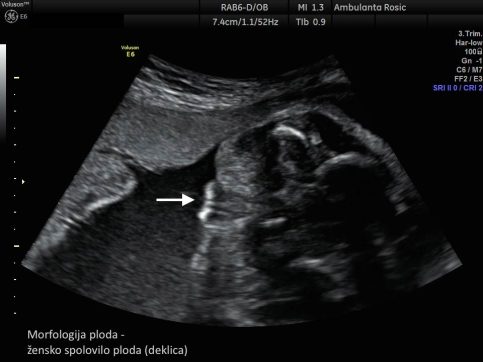

Z morfologijo ploda ugotavljamo normalen razvoj ploda. Ultrazvočni pregled morfologije ploda izvajamo med 19. in 23. tednom nosečnosti. Namenjen je ugotavljanju plodove gestacijske starosti in oceni plodove rasti z merjenjem glavice, trebuha in stegenske kosti ploda ter odkrivanju večjih in manjših razvojnih nepravilnosti pri plodu, ki so povezane s kromosomskimi napakami. S preiskavo opravimo natančen pregled in oceno razvoja ploda in njegovih organov. Pregledamo strukture v glavici, hrbtenico, prsnegi koš, trebuh in okončine ploda. Posebno pozornost namenimo pregledu plodovega srca. Določimo položaj ploda v maternici. Pregledamo tudi posteljico in popkovnico ter ocenimo količino plodovnice. V večini primerov lahko s preiskavo ugotovimo tudi plodov spol, ki pa ga razkrijemo le, če to želite.